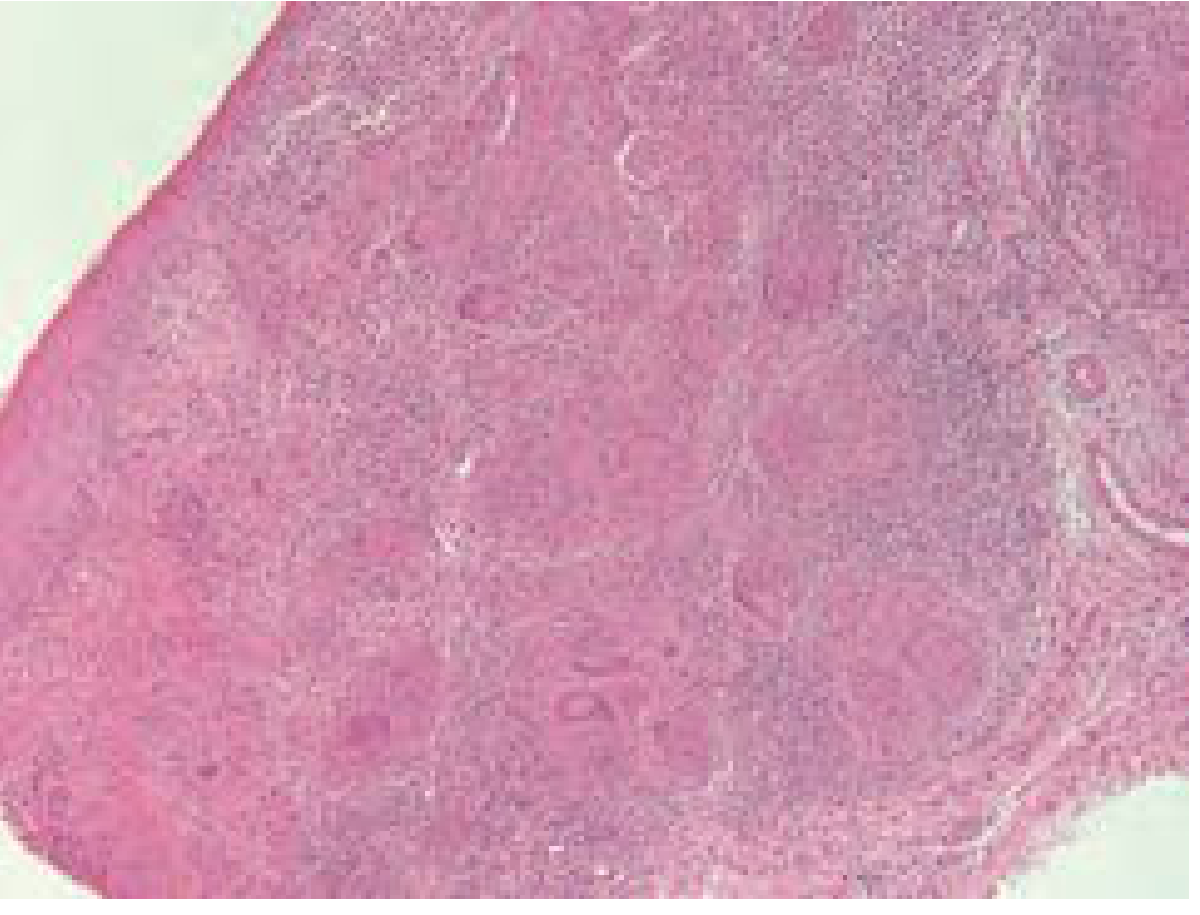

Patients with or without disseminated TB may develop laryngeal disease. Histology shows classic caseating/non-caseating granuloma formation.

Hematoxylin and eosin stain of laryngeal tuberculosis demonstrating granuloma formation

H&E stain of laryngeal tuberculosis showing granuloma formation — Cummings Otolaryngology